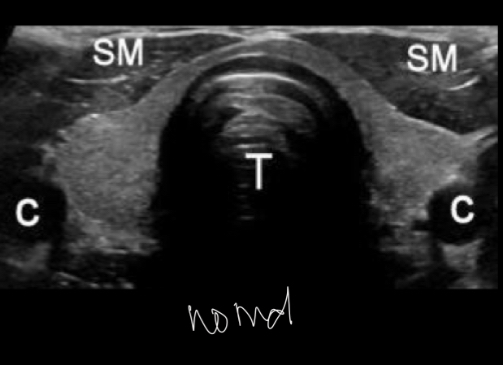

Q

tiroides normal

A

volumen tiroideo en adultos 18-19ml

Forma H